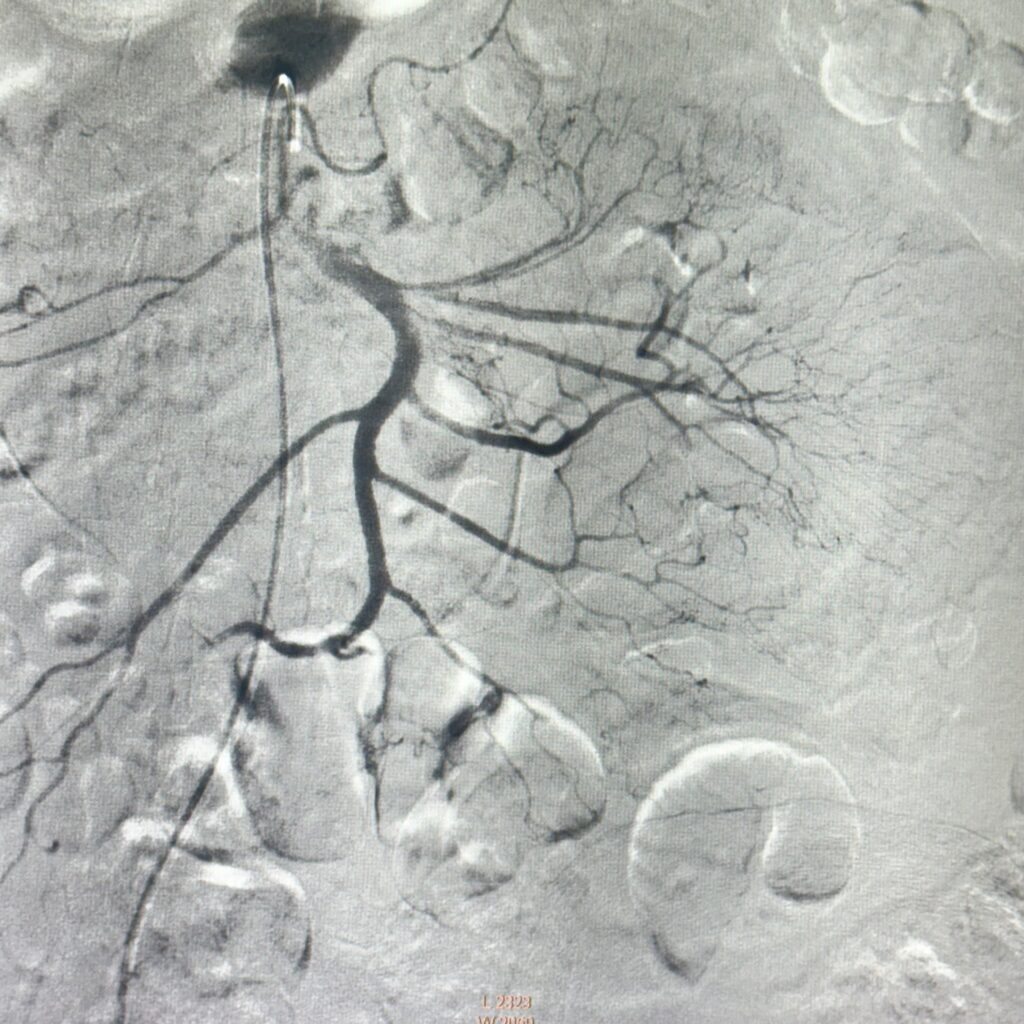

Figura 2: postinjectare de particule resorbabile se remarcă dispariția sângerării

Video 2: postinjectare de particule resorbabile

În ziua a opta de la internare se practică angiografie diagnostică de Arteră Mezenterică Superioară (aspect sugestiv de angiodisplazie jejunală), urmată de embolizare cu particule resorbabile (Gelaspon) a primului ram jejunal. Rezultat optim postprocedural: încetarea HDI, urmată de corectarea progresivă a sindromului anemic (Hb 9,0 mg/dL în ziua a patra postprocedural).